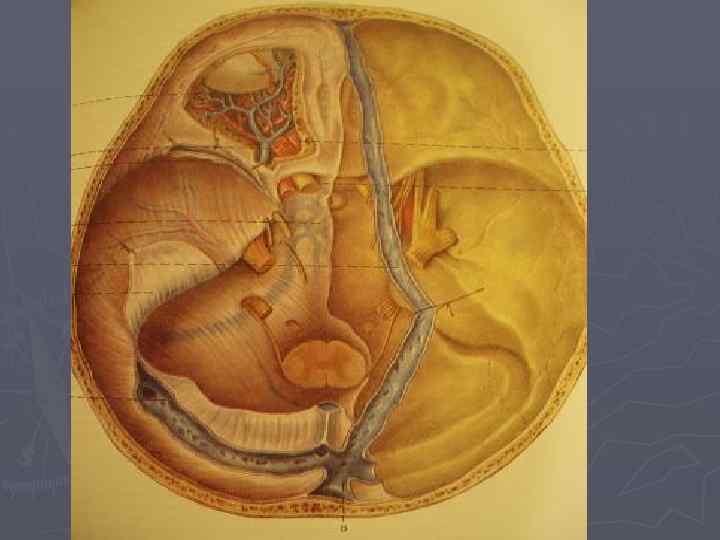

Кровообращение головного мозга

Виллизиев круг ► ► ► 1. внутренняя сонная артерия 2. средняя мозговая артерия 3. передняя мозговая артерия 4. передняя соединительная артерия 5. задняя соединительная артерия 6. задняя мозговая артерия 7. базальная артерия 8. верхняя мозжечковая артерия 9. передняя нижняя мозжечковая артерия 10. задняя нижняя мозжечковая артерия 11. позвоночная артерия

Венозное кровообращение головного мозга